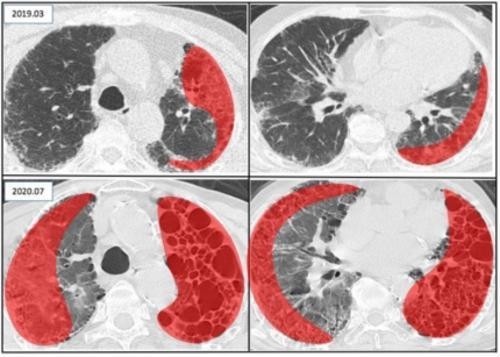

患者的肺部病变明显进展(红色区域为病变位置)

咳嗽、活动后气促 , 检查发现间质性肺疾病 , 这些并没有引起市民赖先生的注意 。 不过 , 近日赖先生的肺“罢工”了:左肺失去换气功能 , 24小时离不开氧气 , 一个月前 , 他的胸部CT提示“右肺散在胸膜下及左肺弥漫性蜂窝肺改变” , 这意味着他部分右肺和几乎全部左肺都失去了换气功能 , 24小时离不开氧气 。

中大五院呼吸与危重症学科主任刘晶介绍 , 该患者入院时血氧饱和度低至75%(正常值为98%以上) , 呼吸频率高达40余次/分(正常值为12至20次/分) , 不能正常说话 , 右肺出现了大面积的磨玻璃渗出影 , 考虑为间质性肺疾病急性加重 。 同时 , 他还患有高血压病、糖尿病、银屑病等多种合并症 。 病情危重 , 这为治疗和护理带来了很大挑战 。